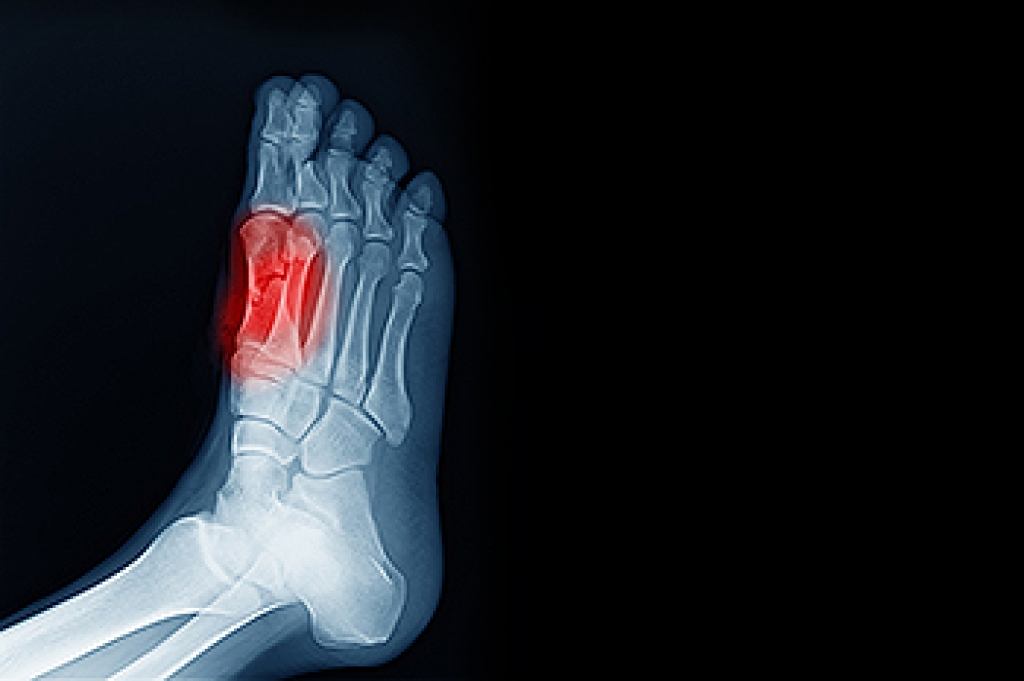

- Broken Foot

- Stress Fractures

Symptoms vary depending upon the injury and in some cases, there may be no symptoms at all. However, in most cases, some form of symptom is experienced. Pain, aching, burning, bruising, tenderness, tightness or stiffness, sensation loss, difficulty moving, and swelling are the most common symptoms.

Treatment

Just as symptoms vary depending upon the injury, so do treatment options. A common treatment method is known as the RICE method. This method involves rest, applying ice, compression and elevating the afflicted foot or ankle. If the injury appears to be more serious, surgery might be required, such as arthroscopic or reconstructive surgery. Lastly, rehabilitation or therapy might be needed to gain full functionality in the afflicted area. Any discomfort experienced by an athlete must be evaluated by a licensed, reputable medical professional.